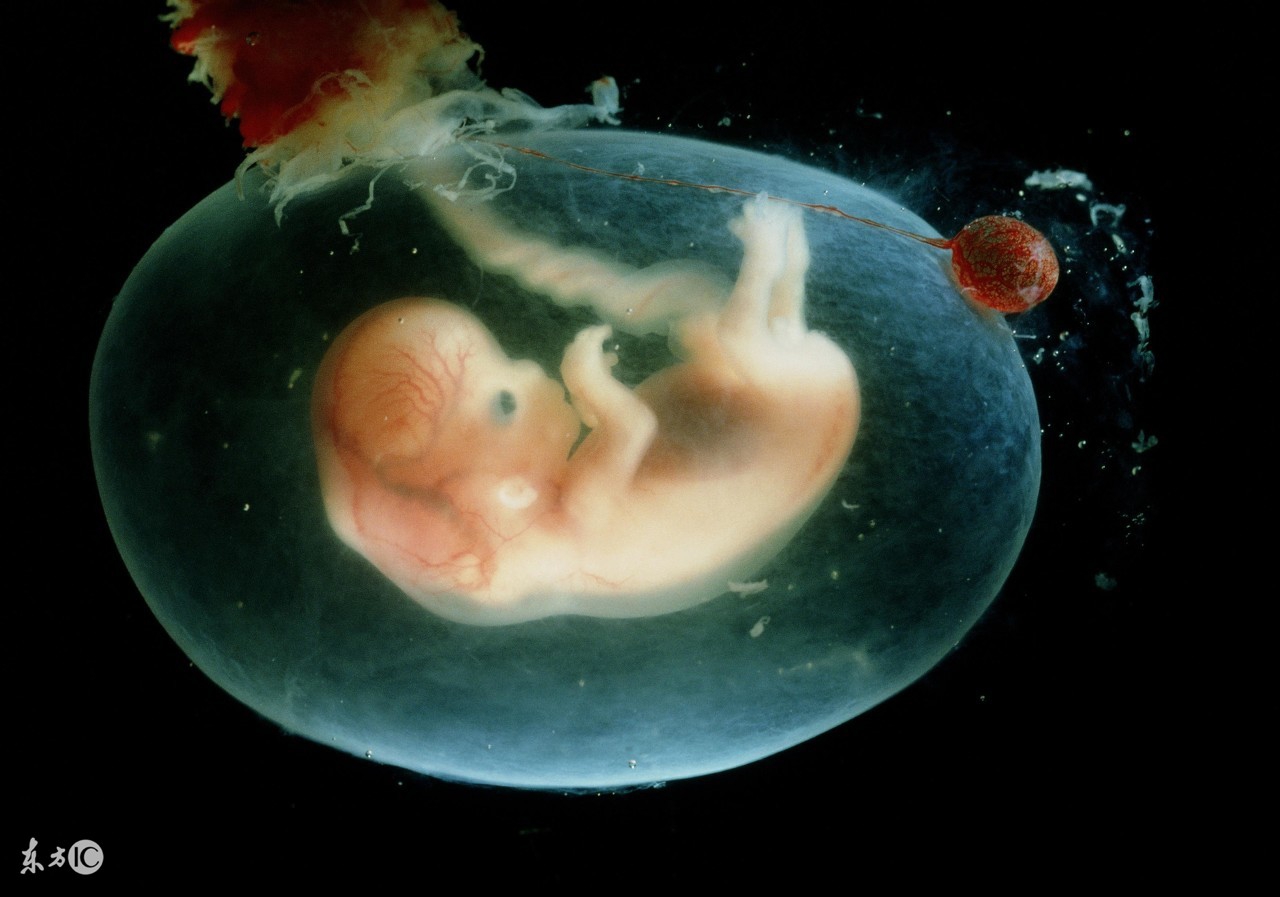

羊水是如何产生的,现在还没有确切的研究结果。但是随着孕期的进展,羊水的“制造原”也会发生变化,这一点是确定的。最初妈妈是制造工厂,但是随着胎儿的发育,其自身的分泌物渐渐增多,孕中期以后宝宝就成了羊水的主要来源。

初期的羊水,妈妈的血液是主要原料。受精卵的卵膜周围涌出的母体血液因细胞间的浸透压力作用而通过卵膜,成为羊水。随后,从怀孕15周起胎儿的皮肤出现角化到20周为止,胎儿的血浆成分和水分渗入羊内膜,也会成为羊水。